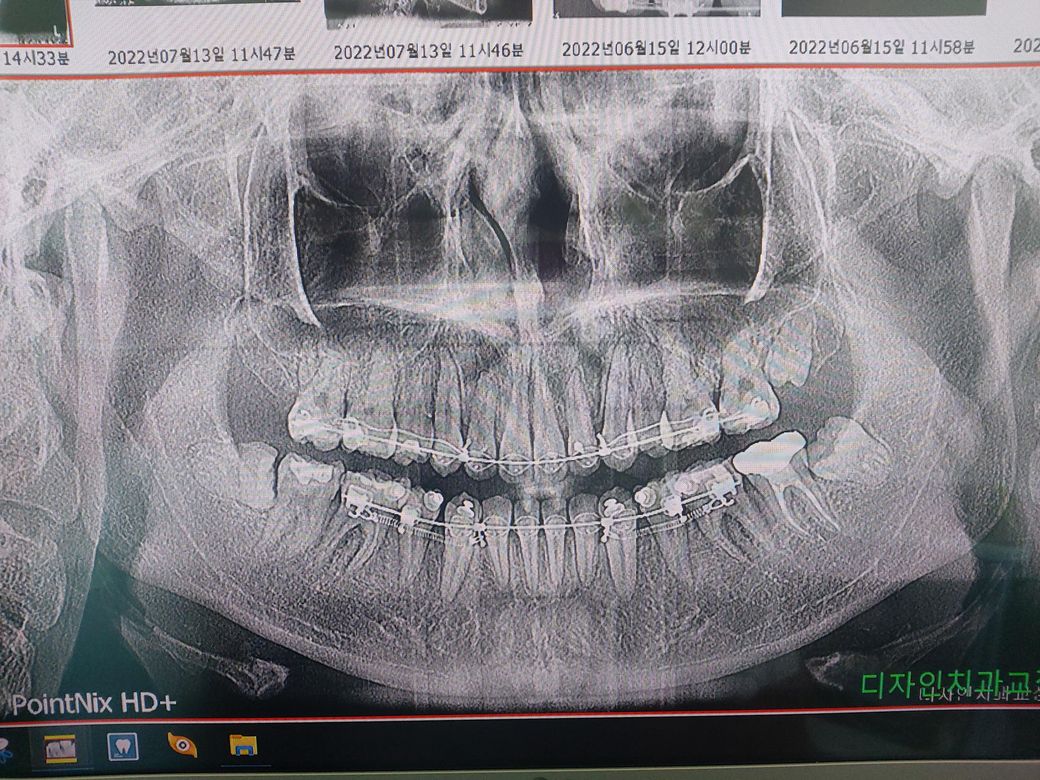

제 기준 왼쪽 아래 맨 안쪽 치아만 차가운 물에 닿거나 강한 접촉이 있으면 아픈데요 교정중이라 매달 검진갈때는 충치있다고 말을 안하더라구요. 그래서 교정때문에 저 치아만 아픈건지 아니면 잇몸이 문제가 생긴건지 사진상으로 다 보이지는 않지만 적어도 심한 충치는 엑스레이로 나오기 때문에 질문합니다

- 안녕하세요. 정진석 치과의사입니다. - 파노라마 사진 상으로 보았을 때는 말씀하신 부위의 큰 충치는 없어 보입니다. 다만 사랑니 때문에 지금의 증상이 나타날 수 있다는 가능성과 교정으로 인하여 양치 습관에 의해 치아 머리 부분이 마모되어 시린 증상이 나타날 수도 있습니다. 또한 급겹한 치아 이동시기에는 지금의 시린 증상이 나타날 수도 있습니다. 지속적으로 나타난다면 해당 부위에 앞서 말씀 드린 것들을 확인해볼 필요가 있습니다. - 아무쪼록 저의 답변이 문제 해결에 작게 나마 도움이 될 수 있기를 기원드립니다. 항상 건강하고, 행복하세요^^ - 정진석 치과의사 드림

- 안녕하세요. 김철진 치과의사입니다. - 사진이 잘못찍혀서 그런지 몰라도 아래쪽 어금니(브라켓달린 마지막치아)에 약간 염증이 잇으신거 같아요. 치과에 가셔서 검진을 받아보세요.